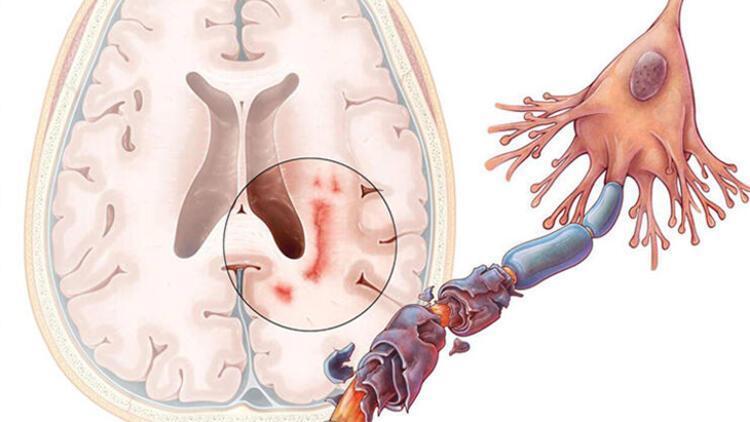

Öncelikle şunu belirtmek gerekir ki bu hastalığa "multipl" denmesinin nedeni, beyin ve omuriliğin birçok farklı alanını etkilemesindendir. Aniden ortaya çıkabilir ya da kaybolabilir. Belirtileri çok çeşitlidir. Hastadan hastaya değişiklik gösterebileceği gibi aynı hastada da zaman içinde farklılaşabilir.

"Skleroz" denmesinin nedeni ise hastalığın beyin ve omuriliğin hasarlı alanlarında sklerozan plaklar yani sertleşmiş dokular oluşturmasıdır. Özetle MS, merkezi sinir sistemini oluşturan beyin ve omurilik üzerinde yıkıcı etkileri olan, kişinin yaşamsal fonksiyonlarını bozan ve ataklarla seyreden bir hastalıktır.

MS, vücudun bağışıklık sistemindeki normal işleyişi bozar. Bilindiği gibi normal şartlarda bağışıklık sistemi bizi hastalıklara karşı korur. Değişik nedenlerle bazen bu sistem vücuttaki normal dokuları da yabancı görmeye başlar ve onlara hücum eder.

Hastalık sinir sisteminin farklı bölgelerini farklı zamanlarda etkileyebilir. İlerleyen hastalık kişinin görme, yürüme, konuşma gibi yaşamsal öneme sahip fonksiyonlarını bozar.